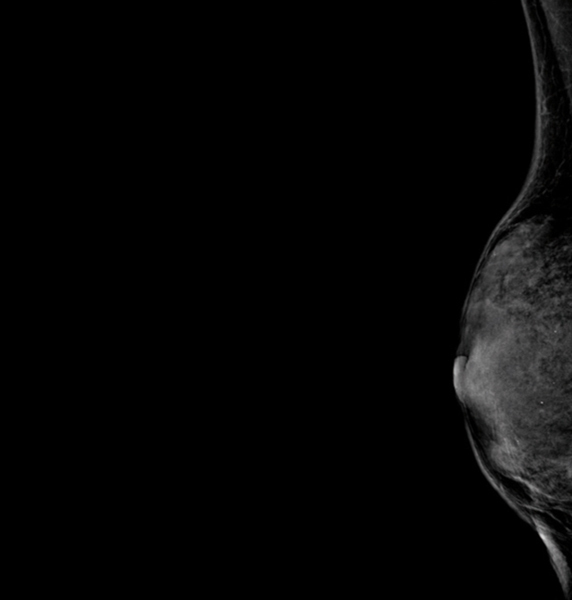

Tumeurs du sein - Petit sein densité de type 4

2. Tumeurs du sein - Petit sein densité de type 4

© Sylvie Lemery - La Revue du Praticien